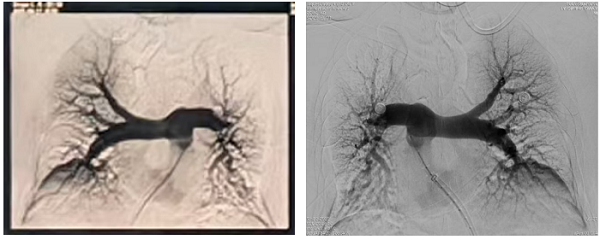

左肺动脉上、下叶动脉血栓(术前影像)

肺动脉主干血栓形成(术前影像)